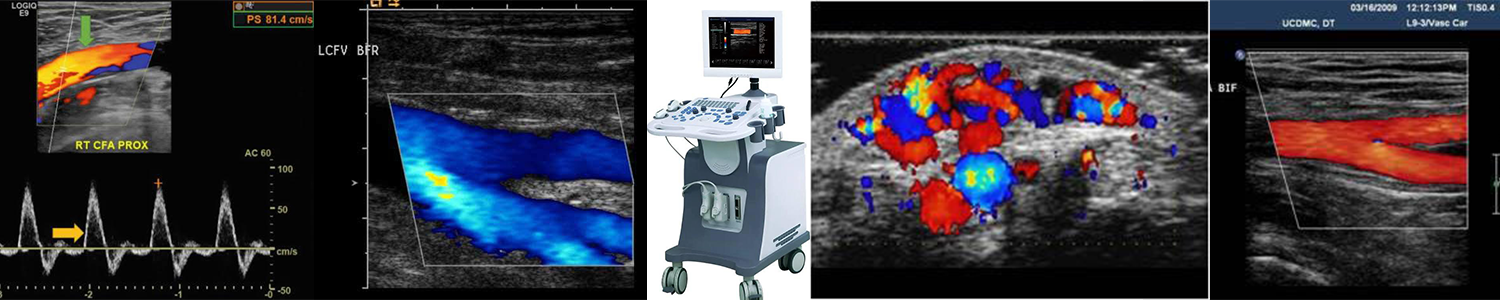

Duplex Ultrasound

The effectiveness of a Duplex Ultrasound largely depends on the expertise of the person performing the scan. For the most accurate results, it should be conducted by a qualified Vascular Sonographer.

Equally important is the interpretation of the scan, which must be carried out by a Vascular Specialist.